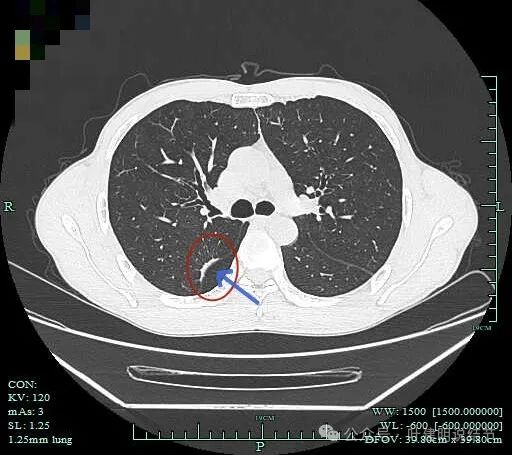

到2023年9月病灶较前进展,或许测量大小变化不明显,但实性成分明显多起来,内部不太致密的部分明显显得较之前密了。

到了2024年5月,病灶整体给人感觉有收缩力了些,内部也更显致密了。